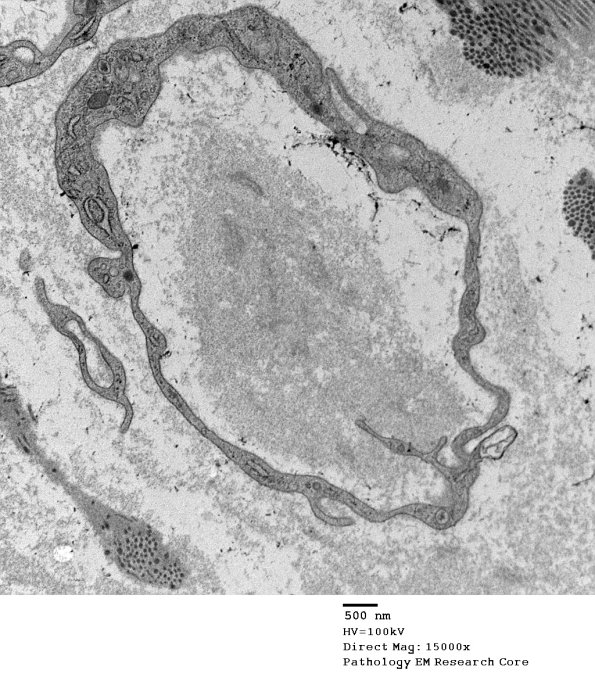

5G4 Renaut body-oma (Case 5) EM 039A - Copy

Higher magnifications showing the variation in content. (electron micrographs)